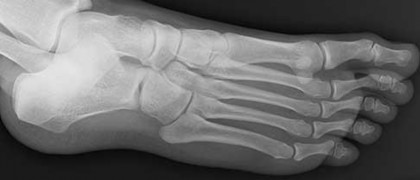

Figures 1a through 1c

Tarsal coalitions occur when primitive mesenchymal cells fail to differentiate and form the

normal articular separations between the tarsal bones of the hindfoot. Overall incidence is difficult to determine because many affected people are minimally symptomatic or asymptomatic. Symptomatic tarsal coalitions typically present in adolescents as a painful flatfoot; however, there are a number of possible presentations, and occasionally symptoms do not appear until adulthood. Most tarsal coalitions are between the calcaneus and the navicular (CN) and the talus and the calcaneus (TC). Although most TC coalitions are across the middle facet, posterior facet coalitions do occur. Plain radiographic evaluation of suspected tarsal coalition is the mainstay for diagnosis. However, coalitions can be bony or fibrous, and making the diagnosis can be difficult. The addition of CT images to distinguish bony definition and MR images to decipher soft tissue can aid in diagnostics. Bony coalitions appear as definite bony bridging between the bones, while fibrous coalitions are suspected when distortion of the bony anatomy is seen. Bony coalitions are best seen on the oblique view (CN) and Harris axial view (TC). There are a number of secondary signs such as the anteater (AE) sign (elongation of the anterior process of the calcaneus as it extends to the navicular as seen on the lateral view [CN]). talar beaking (traction spur of the talar neck thought to result from abnormal stresses as seen on the lateral view [both CN and TN]), and the “C” sign (a continuous cortical contour from the medial talus to the sustentaculum tali [ST]) as seen on the lateral view (TC). A number of newer signs are not as well known, such as a broad mediolateral dimension of the navicular on the anteroposterior (AP) view (the

navicular is wider than the talar head [CN]), nonvisualization of the middle facet on the lateral view (TC), the brick sign (a normal ST is flat, but a distorted ST is enlarged and curved [CN]), and a tapered lateral navicular bone as seen on the AP view (the medial navicular [CN] is much thicker than the lateral navicular).

Figure 1a shows talar beaking (TB), an AE, and an open middle facet (MF). Figure 1b shows a wide navicular (WN), and Figure 1c shows an abnormal articulation between the calcaneus and the navicular, all consistent with a CN coalition.